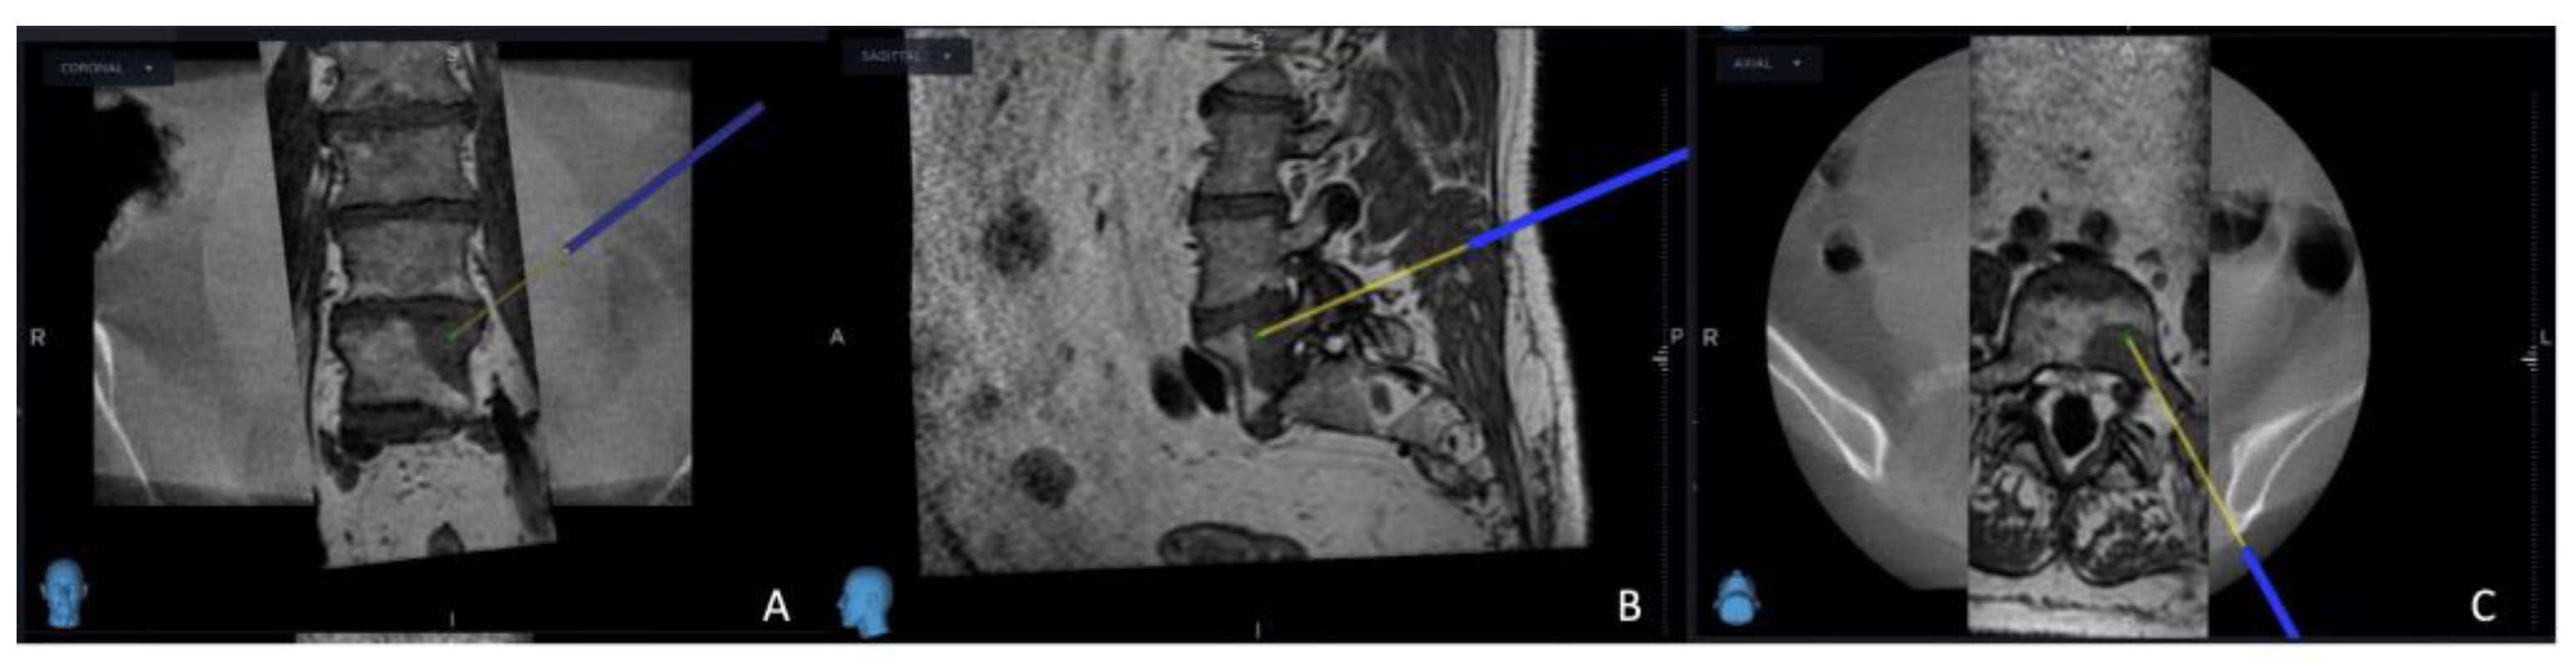

Figure 2. O-arm and MRI fused image, using the MRI image primarily, the yellow projection line, which presents the targeted site for electrode placement: (A) coronal view; (B) sagittal view; (C) axial view.

The intricate procedural sequence embarked upon with the precise determination of the initial entry point, meticulously navigated with the aid of the O-arm scan (Figure 1). Following this pivotal step, the subsequent stage involved the establishment of the targeted point for the upcoming sampling procedure guided by an MRI scan (Figure 2). The surgical roadmap for the needle biopsy procedure was delineated through the utilization of the instrument projection function This was followed by a precise 5 mm skin incision, paving the way for the needle biopsy procedure using the Johnson and Johnson 8G Vertebroplasty Needle.

As the procedure advanced, a repeat O-arm scan was performed on the same spinal segment, with the main goal of verifying the biopsy's precise location, ensuring the accuracy of the electrode placement, and confirming the thermostat's position. This repeat O-arm scan was subsequently integrated with the needle biopsy plan selected from the MRI scan using the same previous "Merge Image" function. This fusion of imaging data served as the guiding framework for the precise execution of the procedure.

Successful needle biopsy sampling was confirmed if the needle biopsy channel's position in the second O-arm scan matched the plan selected in the MRI scan, and the sample was sent to the pathology department for tumor typing. Subsequently, the electrode's and the thermostat's placement were verified by cross-referencing the registered instrument with the merged image (Figure 3). Thermocoagulation was set at 70 °C and lasted for 7 minutes, and the process halted upon reaching a thermostat temperature of 39.5°C. Finally, the Spine Stealth Air reference frame was removed. In cases deemed necessary, Percutaneous Vertebroplasty (PVP) was performed.